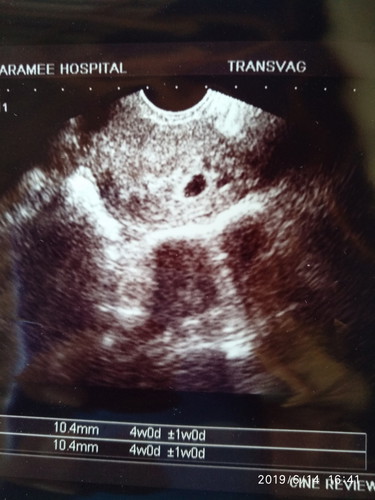

หลังจากมีเลือดสีคล้ำๆออกมาเกิดจากมีเพสสัมพันธ์อาจจะเผลอรุนแรงไปหน่อยค่ะ ได้ไปหาหมอแล้ว หมอตรวจภายใน แล้วก็ซาวด์ทางช่องคลอด เห็นแต่ถุงตั้งครรภ์ แต่ยังไม่เห็นตัวเด็ก ถ้านับจากวันที่ปจด. มาครั้งสุดท้ายก็วันที่11เมษาค่ะ นับได้9W1dแต่ในเครื่องอัลเตอร์ซาวด์ขึ้นแค่4W+1w0d หมอบอกว่า อาจจะเพิ่งตั้งครรภ์ หรืออาจจะท้องลม หมอนัดอีก1เดือนไห้ไปซาวด์ไหม่ ตอนนี้รู้สึกเครียดและกังวลมาก กลัวจะเป็นท้องลมค่ะ ตั้งใจมีน้องมากๆ คัยมีประสบการณ์แบบนี้บ้างค่ะ